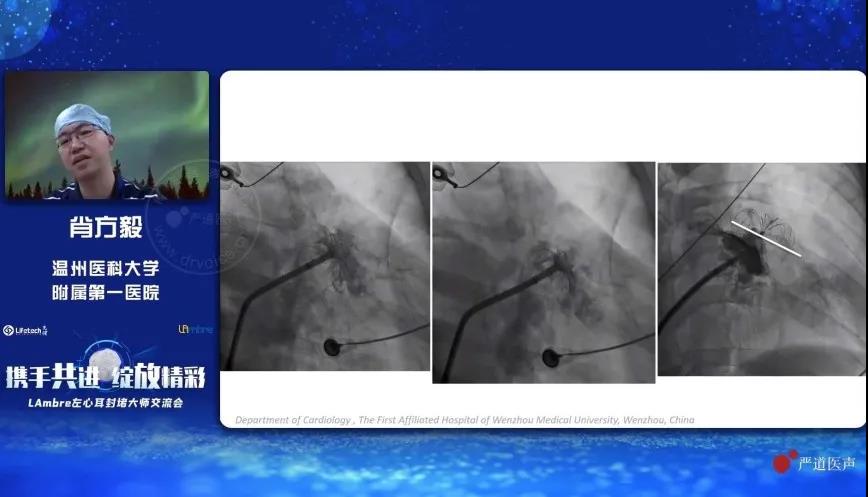

温州医科大学附属第一医院的肖方毅教授分享了使用“渐进式”方法操作LAmbre™左心耳封堵器系统进行手术封堵的技巧。肖教授对比了传统式与“渐进式”两种不同的左心耳封堵器输送方法,并通过详实的统计数据证明,使用“渐进式”方法可有效减少术中回收封堵器的次数,降低封堵器可能对左心耳带来的潜在损伤。此外,肖教授特别指出,虽然“渐进式”方法具有明显的优势,但仍需结合患者的实际情况进行综合考量。